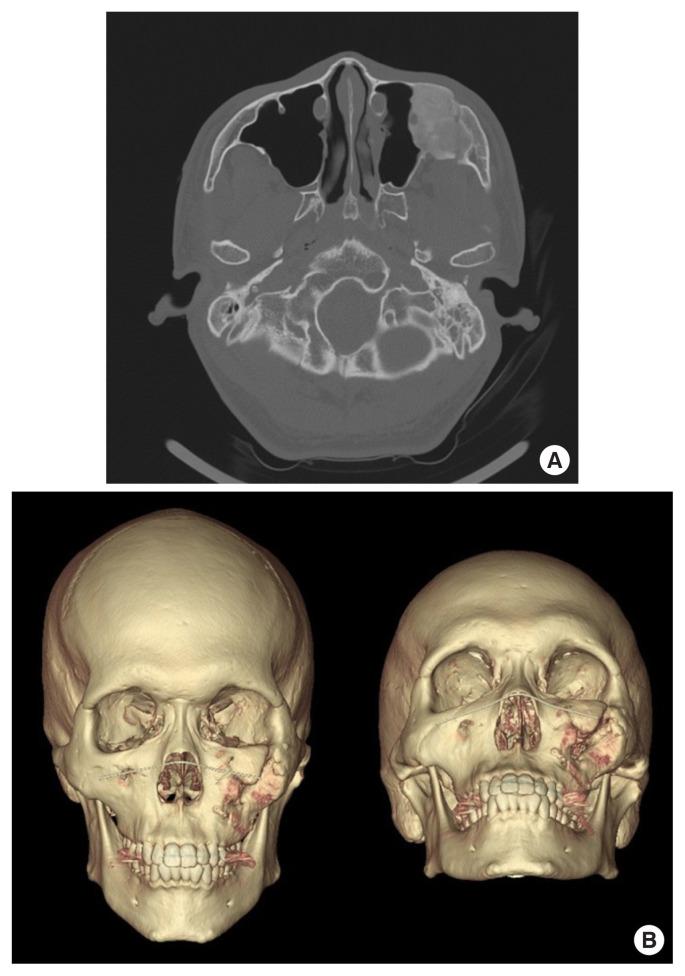

We conducted a retrospective analysis of patients who underwent core extirpation for FD of the zygomaticomaxillary region from 2012 through 2021. Computed tomography (CT) scans were performed 6 to 12 months before the operation, immediately before and after the operation, and during follow-up visits. We performed all operations using the upper gingivobuccal approach, and we extirpated the core of the lesion while preserving the cortical structures of the zygoma and the maxilla to maintain symmetrical facial contour.

In 12 patients with lesions in the growth phase, anteroposterior/mediolateral (AP/ML) length discrepancies and the volume increased between preoperative and immediate postoperative CT scans. All patients' immediate postoperative AP/ML discrepancies were stable up to 12-17 months postoperatively. Postoperative volume showed continuous lesion growth; the median volume growth rate was 0.61 cc per month.